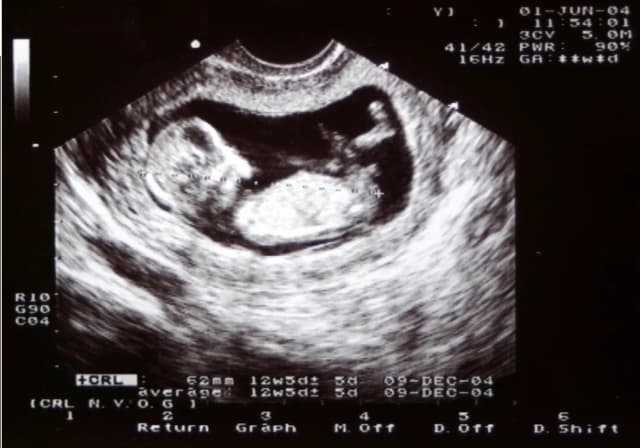

Tag dziwne wrażenia w brzuchu podczas ciąży